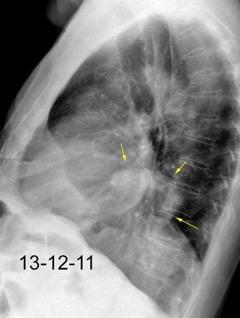

Tromboembolismo pulmonar.

Frecuencia del derrame:

Rx: 32%. TC: 47%

Unilateral. 85%

< 1/3 del hemitórax: 90%

Todos exudados

58% con eritrocitos

21% tabicación lo que causa demora en el diagnóstico

TEP. Empiema pleural. Atelectasia redonda

Porcel JM et al. Analysis of pleural effusions in acute pulmonary embolism: radiological and pleural fluid data from 230 patients. Respirology 2007/ Iguchi T et al. Desquamation of the subpleural lung parenchyma caused by empyema after pulmonary embolism: A case report. Respirol Case Rep. 2022 .